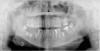

Елена70 Опубликовано 25 августа, 2013 Автор Поделиться Опубликовано 25 августа, 2013 Вот разместила,хочу узнать мнение,что лучше в моем случае отдельные три коронки или мост на 3 импланта? Ссылка на комментарий

Mane Опубликовано 25 августа, 2013 Поделиться Опубликовано 25 августа, 2013 (изменено) импланты из серии ультракоротких - мост здесь будет предпочтительнее и к тому же имплант в позиции 45 стоит не по центру будущей оси зуба а ближе к 44.Если там сделать одиночку, то зуб 45 будет иметь основную нагрузку позади имплантата! Изменено 25 августа, 2013 пользователем Seva Ссылка на комментарий

Art 7 Опубликовано 25 августа, 2013 Поделиться Опубликовано 25 августа, 2013 Вот разместила,хочу узнать мнение,что лучше в моем случае отдельные три коронки или мост на 3 импланта?орпг 2013.JPGв данной ситуации я считаю мостовидный протез соединяющий все имплантаты будет лучше Ссылка на комментарий